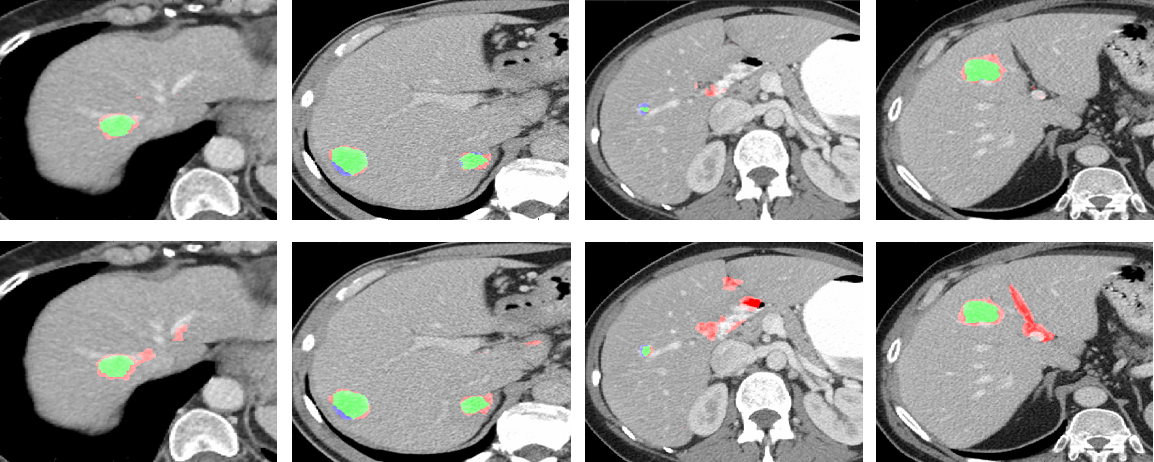

Refer to caption

Figure 4: Examples of lesion detection results showing the variability in lesions size, location and shape. TP marked in green, FP in red and FN in blue.

3.2 Detection performance evaluation

We next evaluated the proposed method on a larger dataset that extended the first to include additional variability overall, from (institution name withheld). Evaluation was performed on the 132 livers with 2-fold cross-validation. Table 2 shows comparison results of our proposed method to other CNN-based systems. Detection results are shown for the entire dataset, as well as for a subset of the larger lesions >> 10 mm, which are the ones mostly recorded by the radiologists and require immediate care. When applied to all lesion sizes, our proposed method resulted in 85.9% TPR and 1.9 FP per liver (FPC) while the binary-class CNN resulted in 80% TPR with 2.8 FPC.

Our multi-class hierarchical approach resulted in similar performance of 86.8% TPR with 1.9 FPC. Using transfer learning for this task (see section 2.2) was not as successful as training from scratch (obtaining 82.8% TPR with 2.54 FPC when applied on all lesion sizes). The detection performance is higher when excluding small lesions (<10mmabsent10𝑚𝑚<10mm), with 93.0% TPR and 1.5 FPC using our parallel multi-class system and 91.8% TPR with 1.56 FPC using our Hierarchical approach. Fig. 4 shows detection examples, demonstrating the ability of our system to detect a variety of lesion sizes. We emphasize that the only difference between the binary-class and the multi-class networks shown in Table 2 is the multi-class description of the non-lesion patches at the final softmax layer of the multi-class network. As can be seen from Table 2, this small network architecture difference yields a huge performance difference.